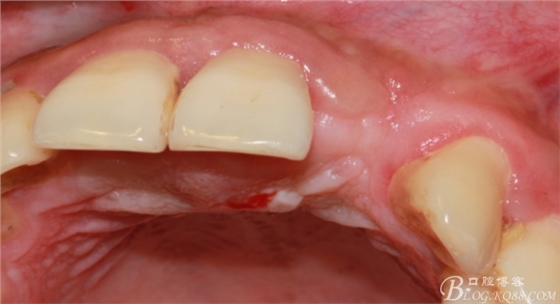

4個(gè)月后,唇側(cè)豐滿度尚可,與鄰牙之間齦乳頭完整。

保留齦乳頭翻小瓣。

翻開后驚喜的發(fā)現(xiàn),術(shù)區(qū)成骨非常好,去除部分骨才暴露那顆長(zhǎng)鈦釘。